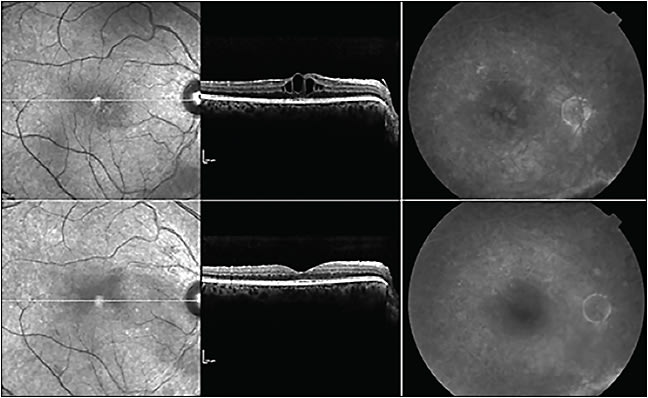

Anti-VEGF strength makes a difference. In our Genentech-sponsored IST testing 2.0 mg/0.05 mL ranibizumab radiation maculopathy trial, higher doses decreased radiation-associated macular edema in recalcitrant cases (Figure 3).29

Figure 3. Clinical response to periodic intravitreal Lucentis (ranibizumab). Top left: A pretreatment fundus photograph reveals a macular hemorrhage, edema, cotton-wool spots as well as exudates. The edge of a relatively large equatorial choroidal melanoma is seen at 10 o’clock. Top right: A pretreatment mid-phase fluorescein angiogram demonstrates capillary drop out, focal areas of non-perfusion, and edema. Lower left: After 6 monthly injections of 0.5 mg ranibizumab, fundus photography demonstrates resolution of most of the cotton-wool spots, exudates, and the retinal hemorrhage. Lower right: A matched-phase fluorescein angiogram shows similar findings plus decreased edema and less leakage from the retinal arteries. Over subsequent years, this patient required high-dose anti-VEGF therapy for suppression. Finally progressing to counting fingers vision due to recalcitrant exudative maculopathy.

COURTESY OF JAMA

Figure 4. A patient with recalcitrant retinopathy following plaque radiation therapy for uveal melanoma. Top left: Despite 12 months of anti-VEGF therapy, macular edema persists with a central fovea thickness of 436 µm on optical coherence tomography (OCT). Top right: Pre-high-dose fluorescein angiogram in arteriovenous phase demonstrates persistent macular edema. Bottom leftt: After12 monthly injections of 2.0 mg ranibizumab, the macula resumes its normal contour on OCT, with an CFT of 228 µm. Bottom right: Also after 12 monthly injections of ranibizumab 2.0 mg, an arteriovenous phase fluorescein angiogram reveals a marked reduction in macular edema.

COURTESY OF WICHTIG PUBLISHING